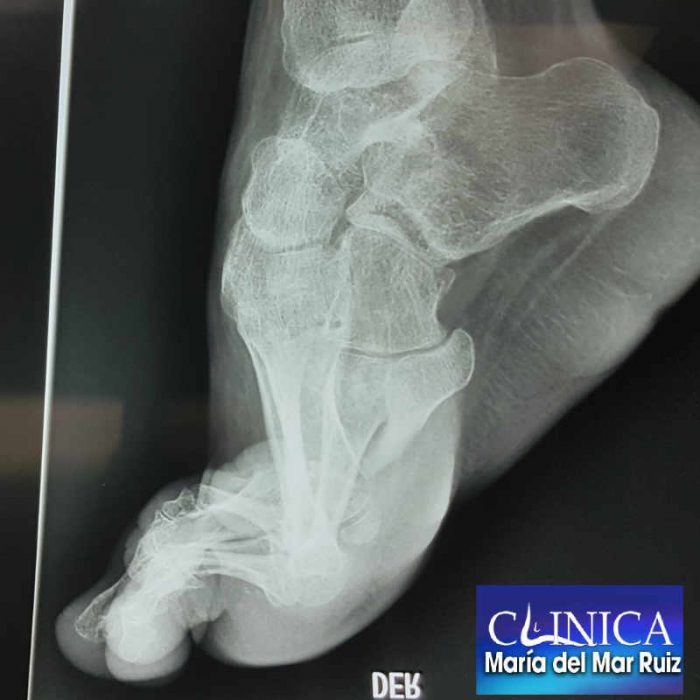

Pie Equino Varo o Pie Zambo

Pie equino varo o pie zambo Clínica María del Mar Ruiz Pie Equino Varo Unilateral Entre las más comunes se encuentran los. Este término describe una variedad de anomalías congénitas del pie en las que este presenta un forma o posición torcida, impidiendo que se. Existen diversas causas que pueden contribuir al desarrollo del pie equino. Equinovarus foot is an acquired foot deformity commonly seen in pediatric patients with cerebral palsy, spina bifida, and duchenne. Pie Equino Varo Unilateral.